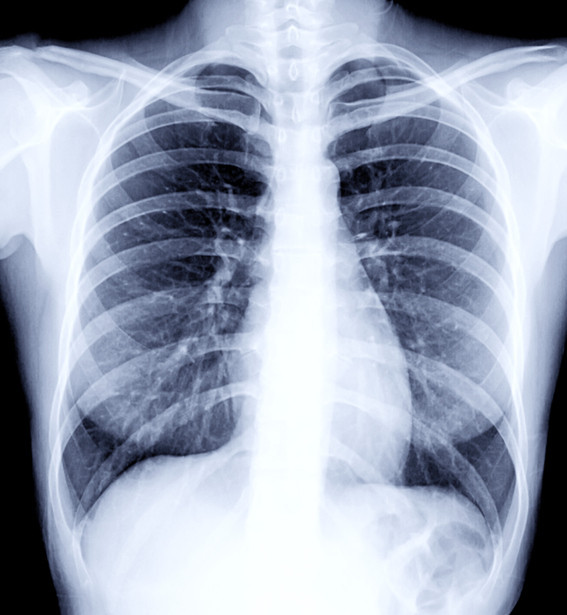

वैदेशिक रोजगारीको लागि अनिवार्य हुने स्वास्थ्य परीक्षणमा Chest X-ray गरिन्छ। यसमा फोक्सो (lungs) को अवस्था हेर्ने गरिन्छ।

छातीमा दाग भन्नाले प्रायः फोक्सोमा पुरानो रोग, संक्रमण वा चोटपटकपछि बाँकी रहेको ‘scar’ (घाउको निशान) लाई जनाउँछ। यो दाग प्रायः सामान्यतया मानिसलाई थाहा नहुने गरी हुन्छ र X-ray गर्दा मात्र देखिन्छ।